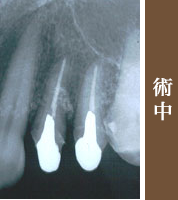

再生療法を行いました、歯の周りの骨量が回復しています 。

噛み合わせの問題もあり被せもので改善しました。歯の周りの骨も再生し、抜歯せずにすみました。